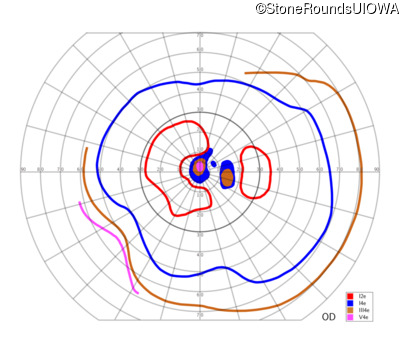

This 59 year old woman first noticed a reduction in her visual acuity and photophobia in her late teens.

| AD Cone and Cone Rod Dystrophy | GUCA1A | Glu155Gly GAG>GGG | AD |

Glu155Gly GAG>GGG